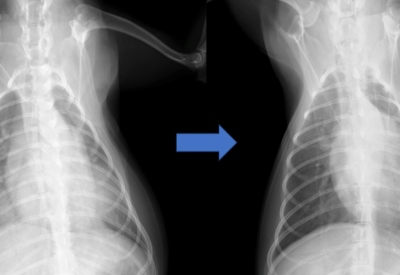

胸部レントゲン検査にて心陰影の拡大と肺野の透過性の低下が認められました。